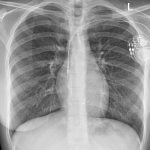

- Φυσιολογική Βηματοδότηση με Left Bundle Branch Pacing – Περιστατικό 2:1 κολποκοιλιακού αποκλεισμούby Ioannis KoulouridisΑσθενής με συμπτωματικό 2:1 κολποκοιλιακό αποκλεισμό (AV block) προσήλθε με ζάλη και κόπωση, με βασικό ρυθμό φλεβοκομβικό και ασταθή αγωγή προς τις κοιλίες. Αποφασίστηκε τοποθέτηση μόνιμου βηματοδότη με τεχνική Left Bundle Branch Pacing (LBBP), με καθοδήγηση μέσω του μεσοκοιλιακού διαφράγματος για επίτευξη σύλληψης του αριστερού σκέλους. 🔹 Στο προεγχειρητικό ΗΚΓ (1η εικόνα) καταγράφεται 2:1 AV[…]